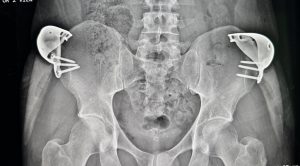

A 40mm wide iliac plate is inserted and positioned on the side or lateral border of the iliac crest not on top of it. This ensures that increased pelvic width is obtained.The plate only need to be positioned on the widest part of the iliac crest which is the anterior two-thirds of the crest. Three anterior screws are placed through the plate into the bone in a bicortical fashion.

A hooked silicone hip implant is fitted into the hollow chamber of the titanium plate. This prevents any risk of implant migration and implant sag with edge folding. The silicone hip implant pocket is developed at the deep subcutaneous level on top of the deep fascia of the gluteus medius muscle. After a drain is placed soft tissue closure is performed in multiple layers with resorbable sutures. The closure line is covered with micropore tape and a circumferential hip wrap is applied